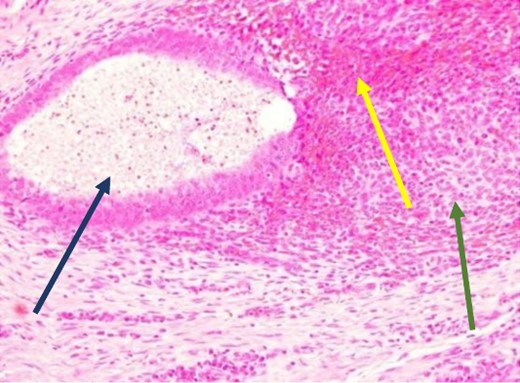

Low power view showing endometrial glands and stroma in abdominal wall tissue consistent with endometriosis (H&E).

High power showing endometrial gland and stroma with hemorrhage consistent with endometriosis (H&E).

High power showing plasma cells in the stroma consistent with chronic endometritis (H&E).